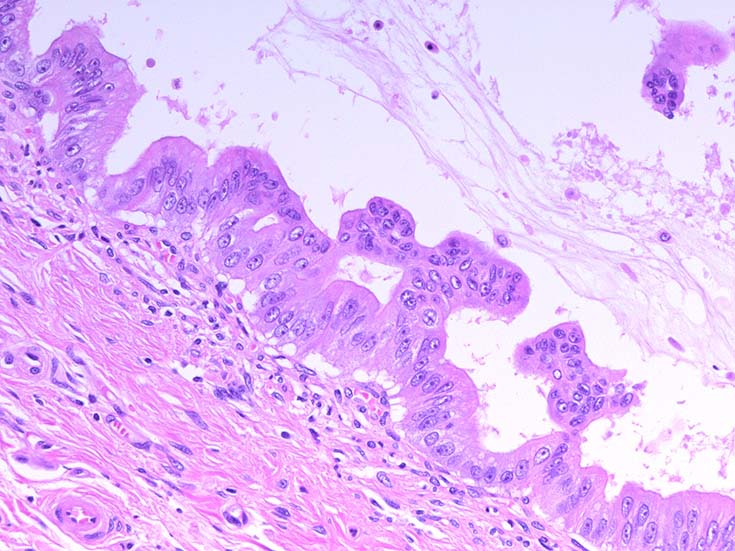

膵上皮内腫瘍性病変 pancreatic intraductal neoplasm(PanIN)*16

Low-grade PanINとhigh-grade PanINの分類

low-grade PanIN

high-grade PanIN

PanINの図譜はJohns Hopkins The Sol Goldman Pancreatic Cancer Research CenterのHome page*19から引用.

1. PanIN-1; PanIN発生の初期段階. 組織学的に, 核異型を伴わない, 核の極性が保たれている.